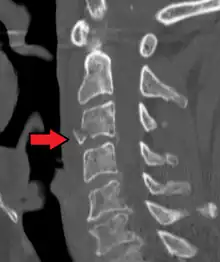

On CT scan or X-ray, a cervical fracture may be directly visualized. In addition, indirect signs of injury by the vertebral column are incongruities of the vertebral lines,[7] and/or increased thickness of the prevertebral space:[8]